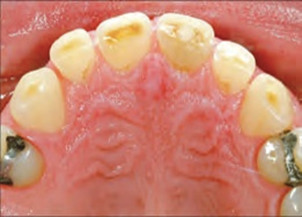

The contact between teeth requires investigation into their tribological behavior focusing on the enamel wear process against natural teeth and/or artificial teeth, allowing us to obtain useful information on the tribological behavior of restorative materials. Considering the complex inter-oral environment and biomechanics, the wear processes of artificial dental materials are very complicated and normally include abrasion, attrition, corrosion, fretting wear, and fatigue. These processes occur in various combinations to cause surface loss of materials in the mouth. Tooth surface loss most often results from the natural tooth-to-natural tooth and/or natural tooth-to-restoration contact (Figure 3). It is often accelerated by restorations—this is especially true with opposing ceramic restorations. The reduction of the surface might lead to a variety of problems. These include loss of enamel, loss of dentine, teeth fracture, hypersensitivity, compromised aesthetics, misshapen teeth, loss of tooth vitality and problems in chewing, and possible jaw problems as a result of reduced facial vertical dimension in patients with generalized tooth surface loss (Figure 4). These types of bio-tribological behaviors are very much significant in human dentistry.